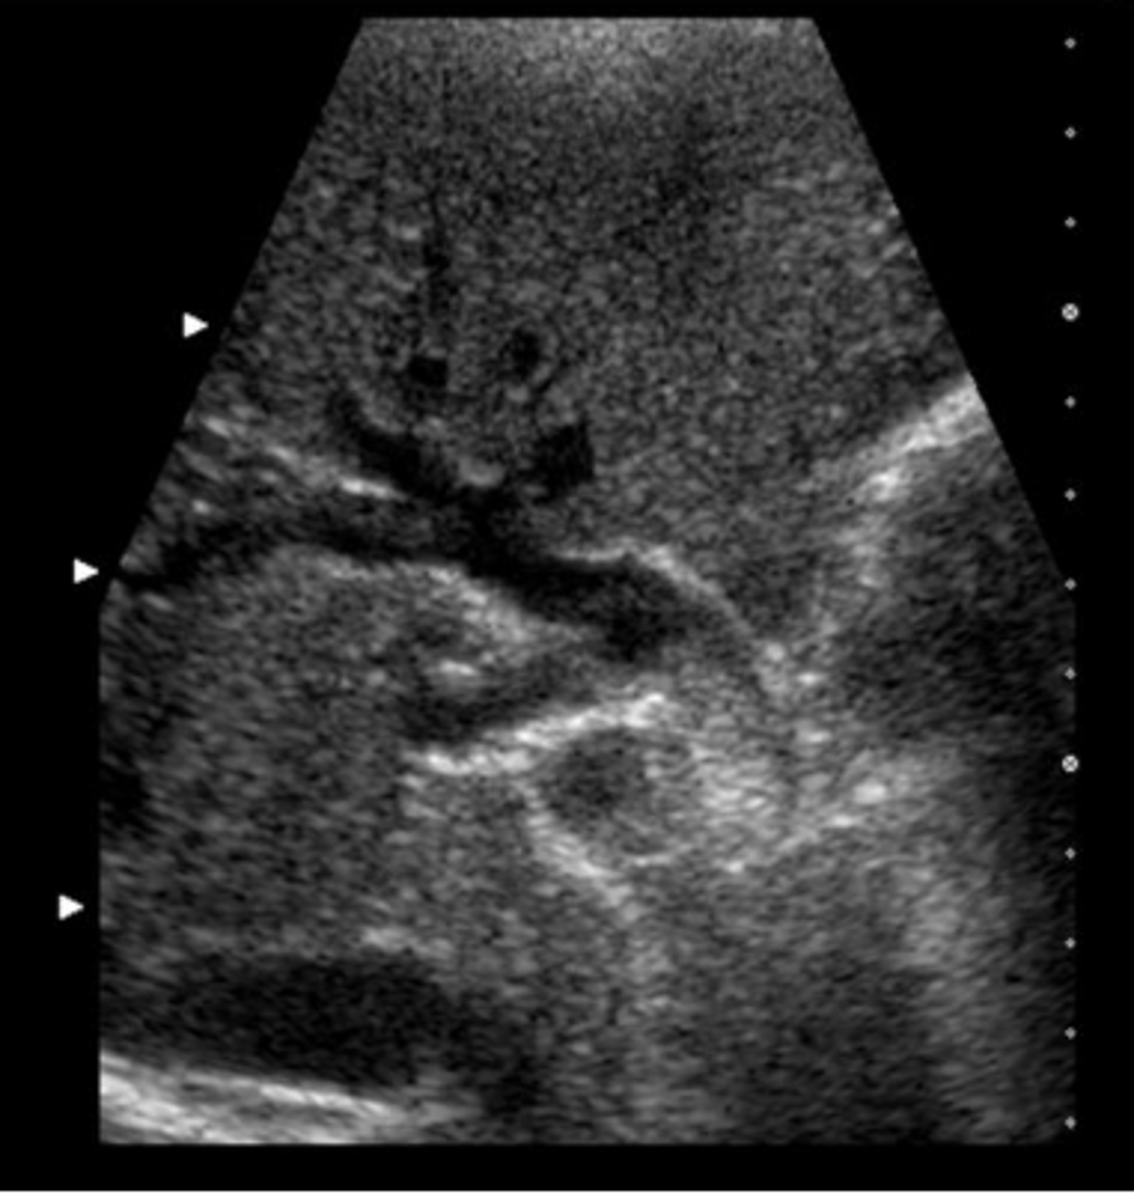

c. pancreatic head pseudocyst

This image was obtained in a 48-year-old male referred for an abdominal ultrasound because of abnormal liver function tests. Which of the following best describes the findings?

a. ectopic location of gallbladder

b. pancreatic head carcinoma

d. fluid in the duodenum

e. peripancreatic lymphadenopathy